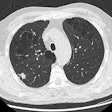

Novel study investigates impact of marijuana on lungs